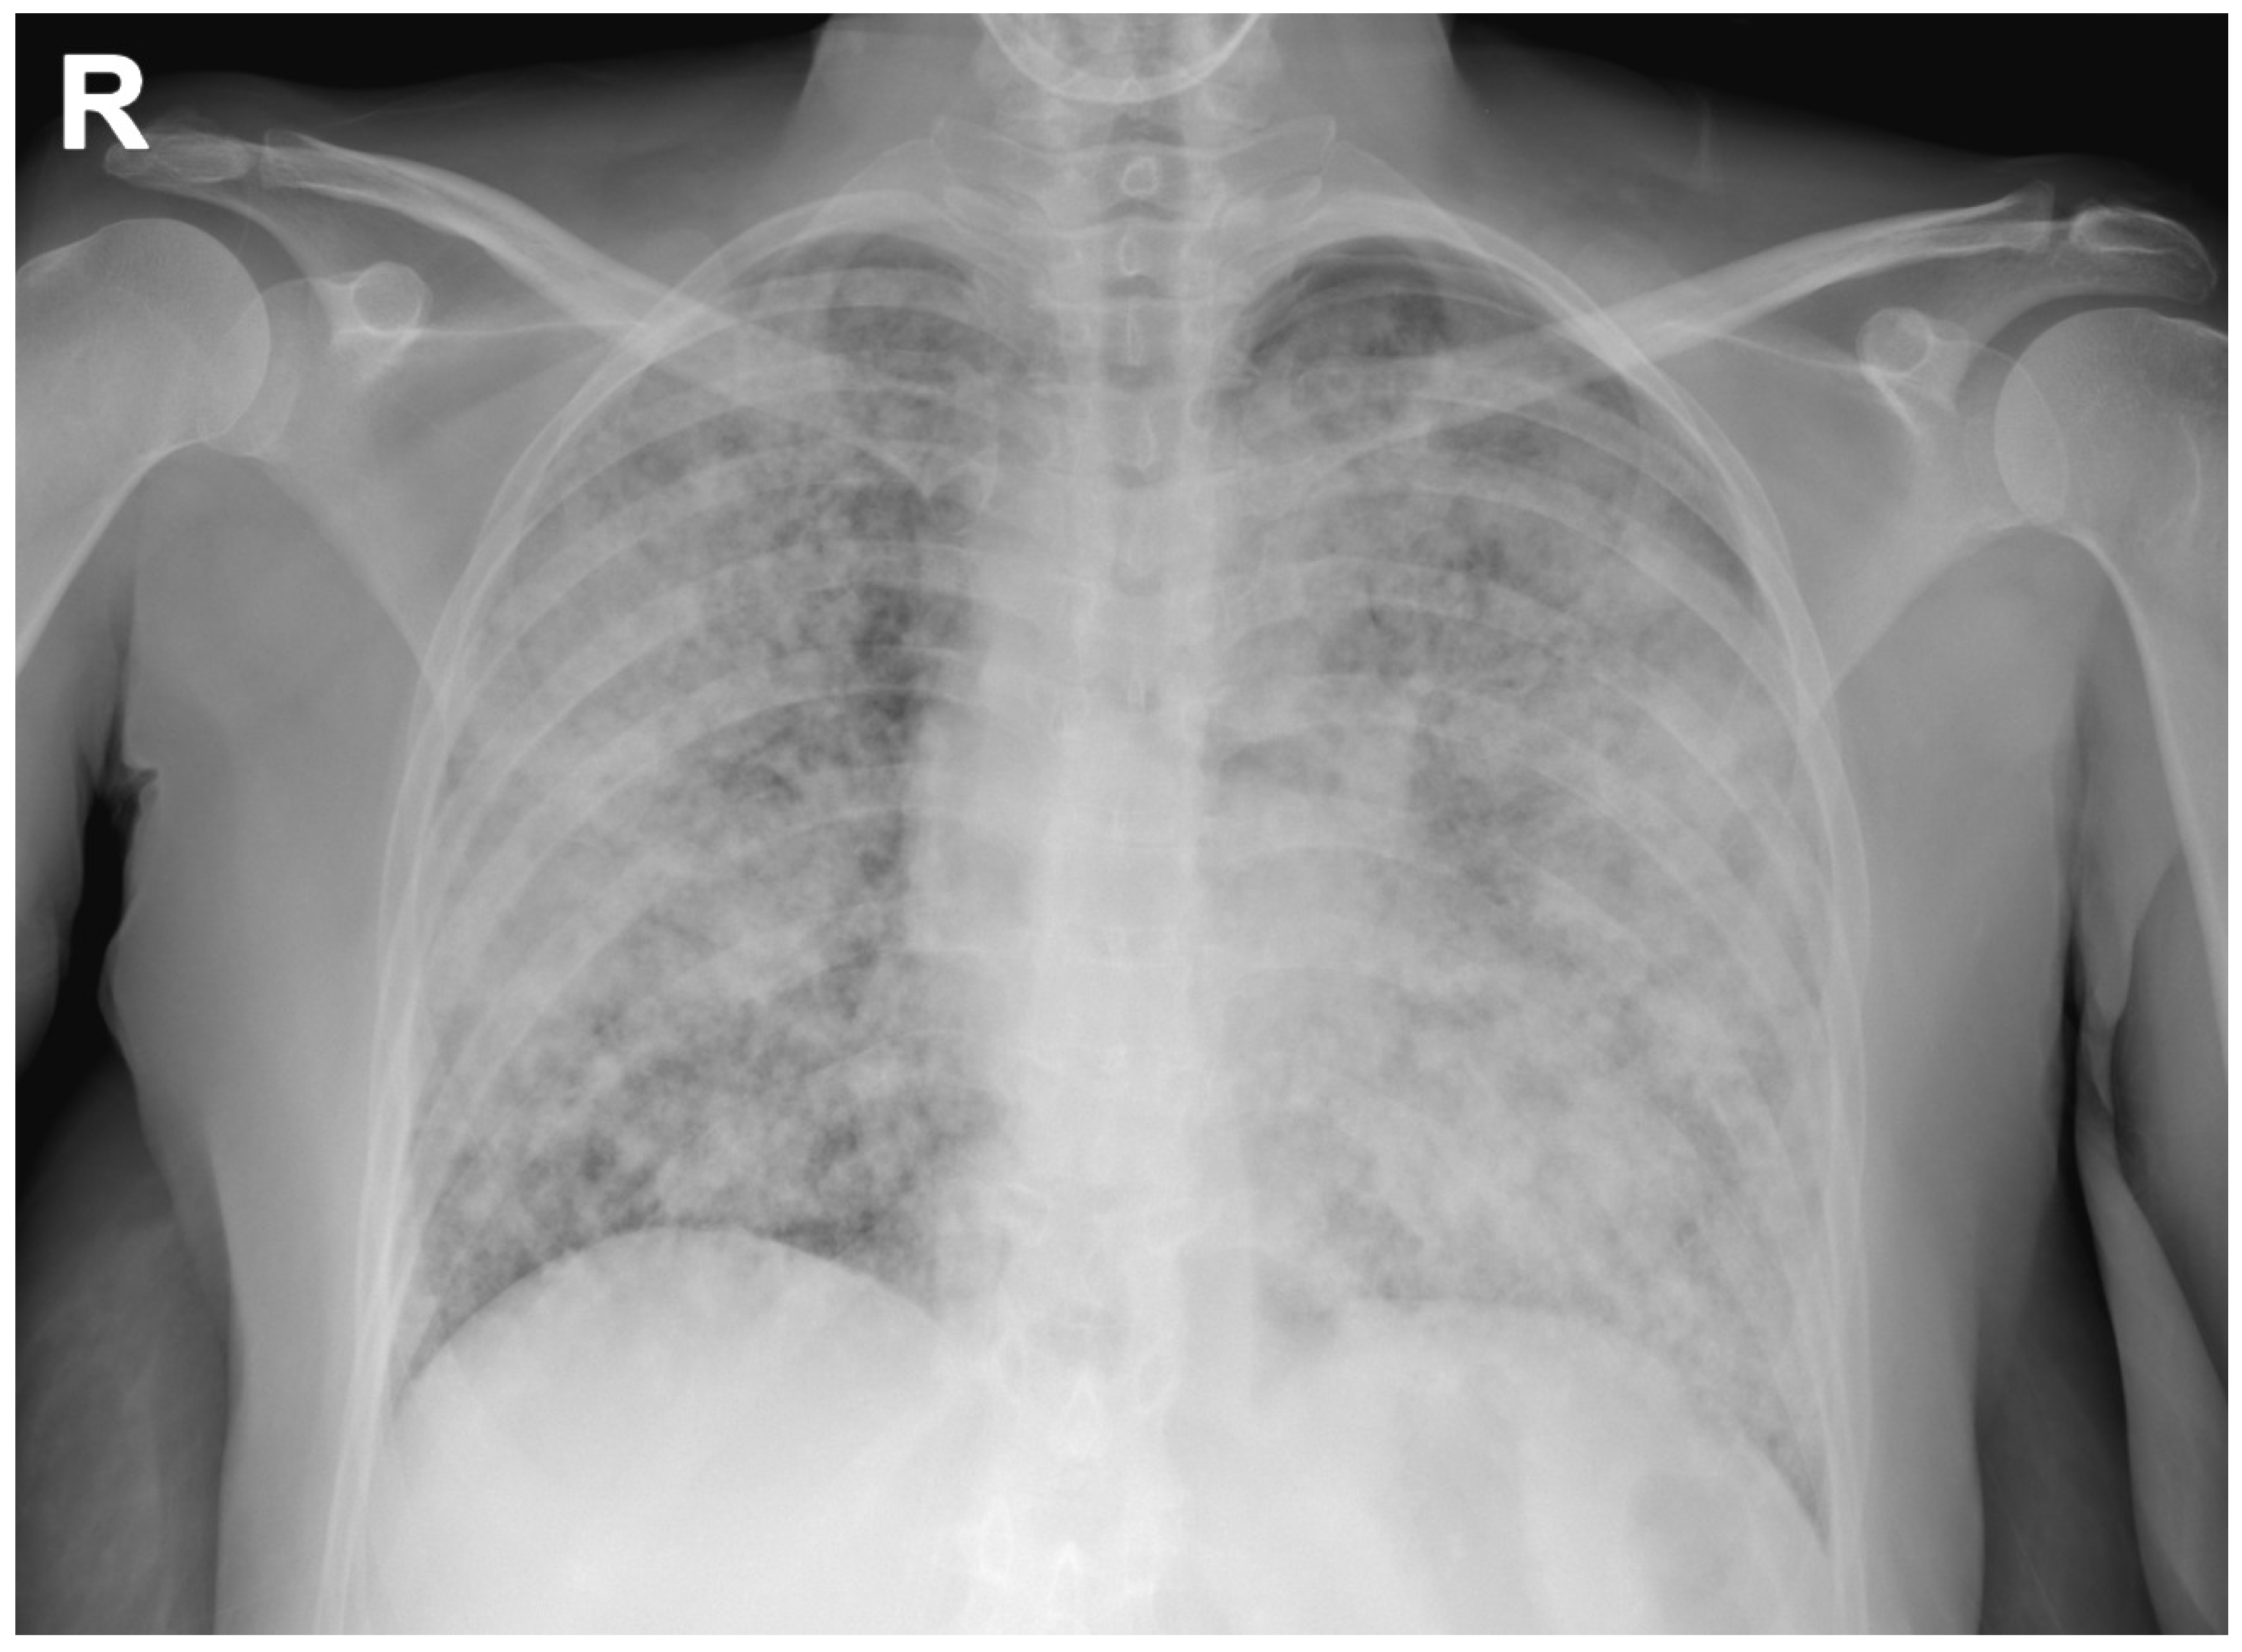

posteroanterior view of chest Xray showing reticular interstitial Chest X Ray Usual Interstitial Pneumonia [1] the scarring (pulmonary fibrosis). iips include seven entities: a usual interstitial pneumonia (uip) pattern on chest ct scans is highly suggestive of uip pathologic findings; Idiopathic pulmonary fibrosis, which is characterized by the morphologic pattern of usual interstitial pneumonia. usual interstitial pneumonia (uip) is a form of lung disease characterized by progressive scarring of both lungs.. Chest X Ray Usual Interstitial Pneumonia.